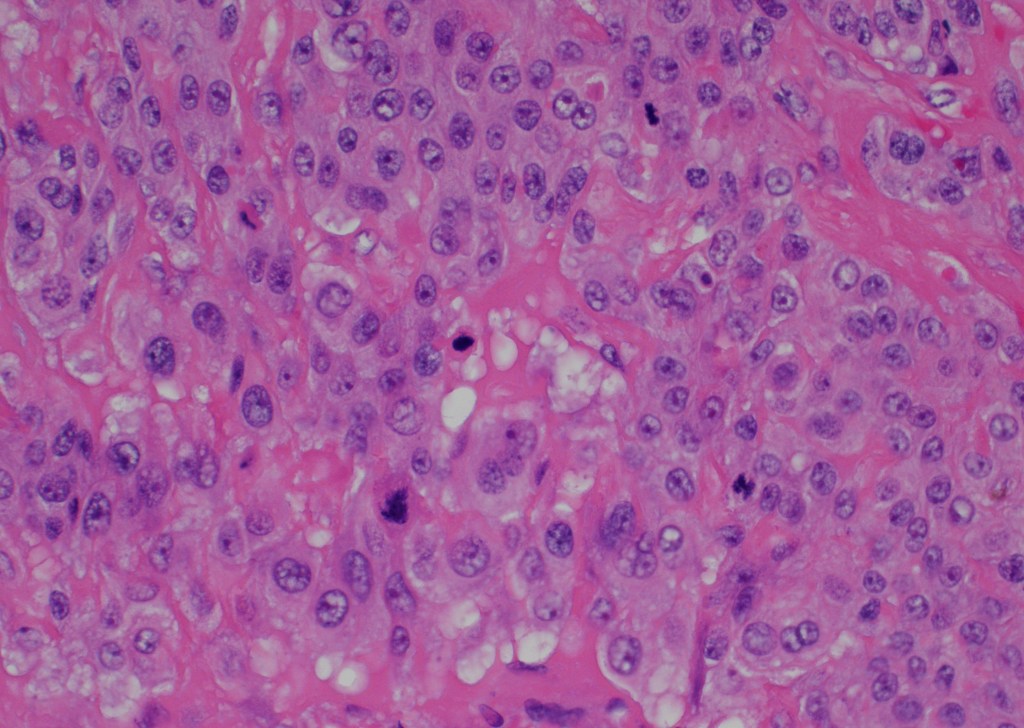

Microscopic examination: the lesion revealed nodular, expansile growth. The nodules were composed of epithelioid cells with abundant eosinophilic cytoplasm, frequent mitotic figures, and the background of necrosis. The nodules and the cells were embedded in the background of hyaline material (Figures 1-4). The cells were positive for GATA-3, alpha inhibin, cytokeratin, and negative for ER, PR, beta-hCG, p16, p53. The diagnosis of the epithelioid trophoblastic tumor (ETT) was rendered. Two years later she presented with new lung nodules. The biopsy showed a metastatic epithelioid trophoblastic tumor with the same immunophenotype. Immunohistochemistry for PD-L1 was positive.

Figure 4

Grossly, the tumor is a distinct lesion or a mass (required for the diagnosis). Microscopically, the cells grow in a nodular pattern with pushing invasion into adjacent structures. The neoplastic cells are large with abundant cytoplasm, arranged in nests and sheets. The mitotic rate is variable, and it ranges from <10 per 10 high-power fields to brisk mitotic activity. High mitotic count is a poor prognostic sign. The background of eosinophilic hyaline-like material is frequently present. Many times, like in our example, extensive geographic necrosis is noted.